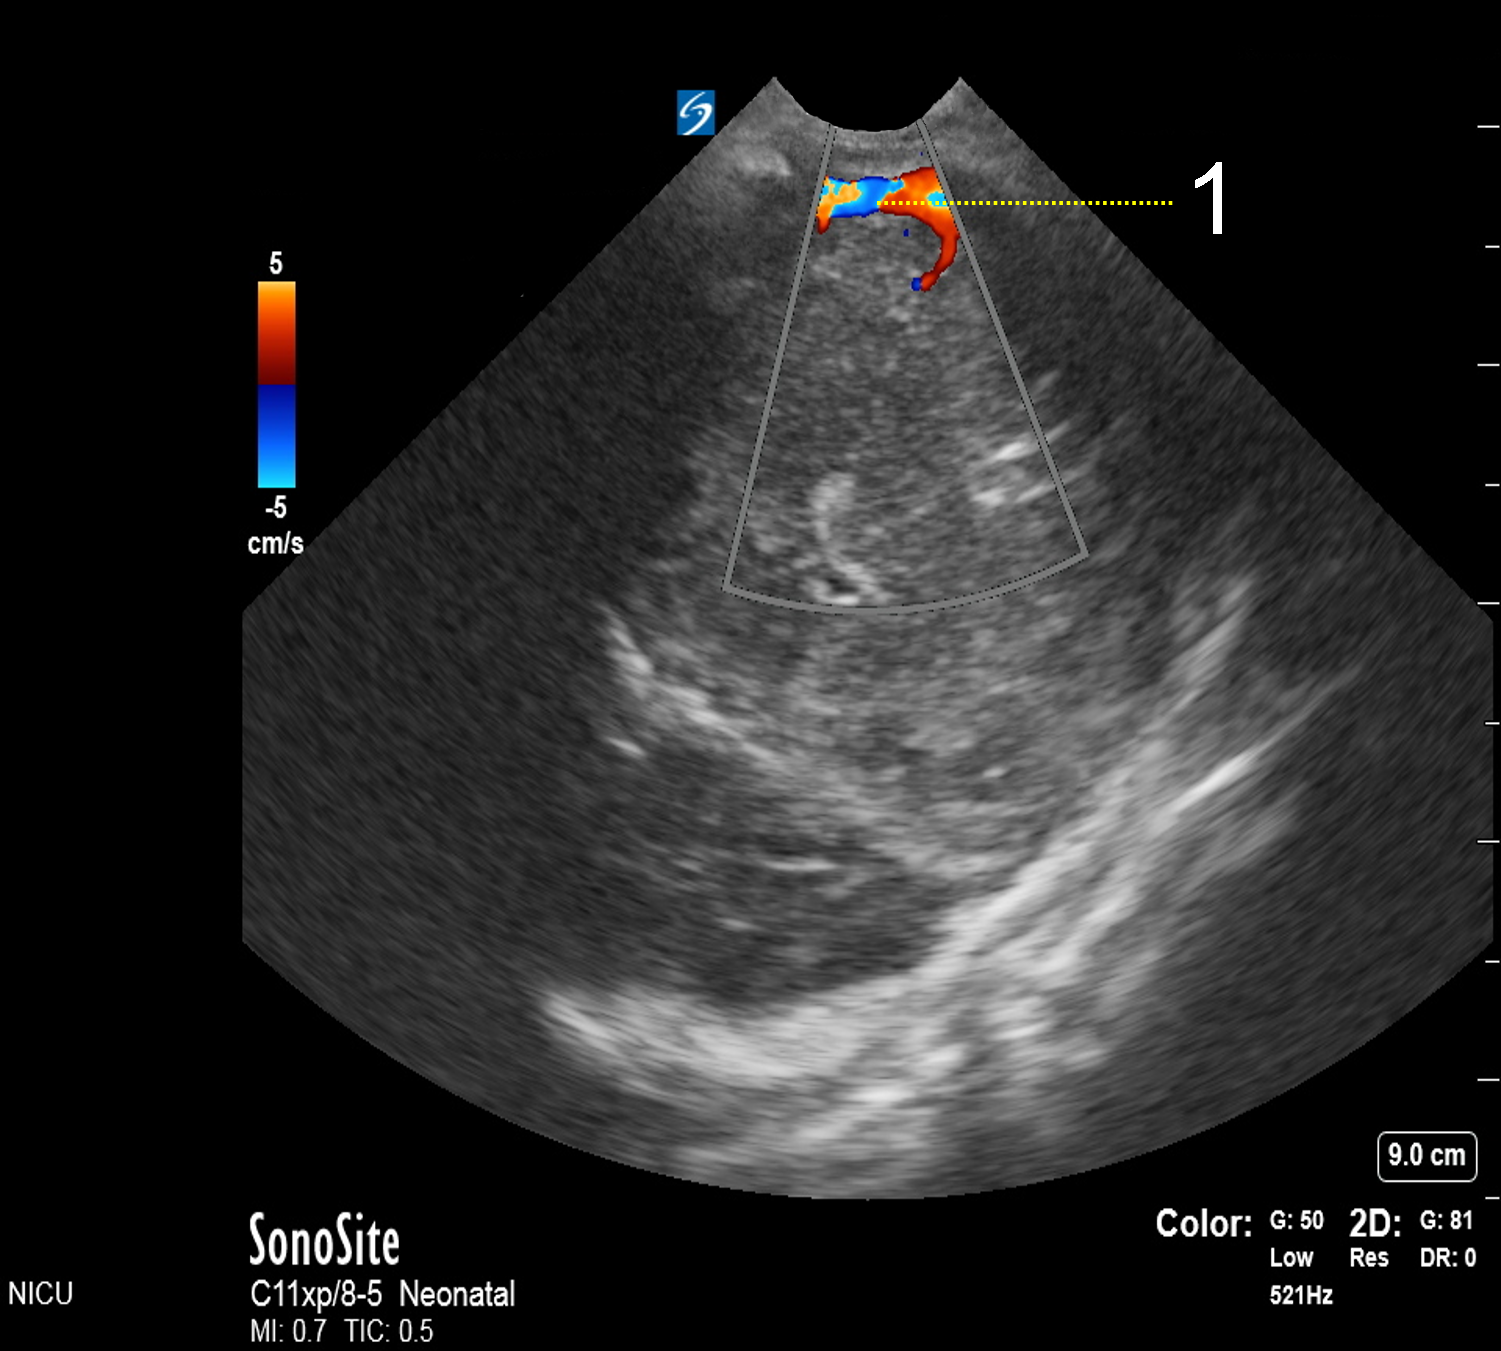

Neonatology Transverse Sinuses 2 Image

Transverse Sinuses